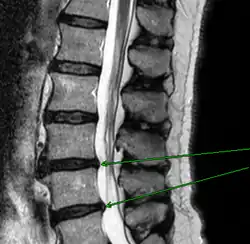

Патология

Механическое смещение одного из поясничных позвонков, переохлаждение, локальная инфекция, опухоли, деградация тканей, могут привести к воспалительному процессу в позвоночно-двигательном сегменте, последующим мучительным болям, вынужденным положениям тела. Очень распространённой причиной патологии в поясничном отделе позвоночника является неверное распределение нагрузки на поясничный отдел позвоночника, когда дополнительный вес (а иногда и собственный вес) поднимаются с единственным рычагом в поясничном отделе позвоночника. Частым заболеванием в поясничном отделе позвоночника являются грыжи межпозвоночных дисков — выпячивания пульпозного ядра диска за пределы его фиброзного кольца. В 48 % случаев межпозвоночные грыжи локализуются на уровне L5-S1 пояснично-крестцового отдела, в 46 % случаев — на уровне L4-L5, и лишь в оставшихся 6 % случаев — между другими позвонками поясничного, шейного или грудного отделов позвоночника.